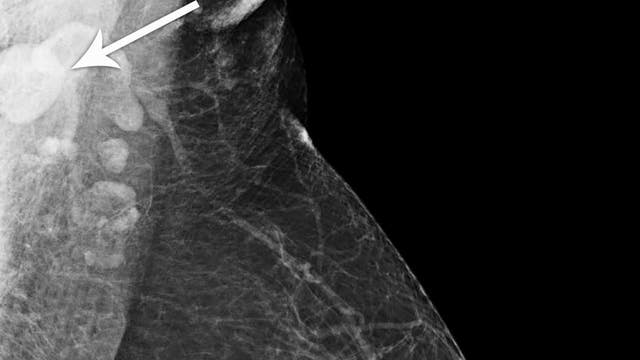

Swollen lymph nodes can be side effect of COVID-19 vaccine and confused for cancer, doctors say

Doctors are working to spread the word that swollen lymph nodes are a normal and expected side effect of the COVID-19 vaccine in an effort to ease patients’ fears of cancer and avoid unnecessary testing.